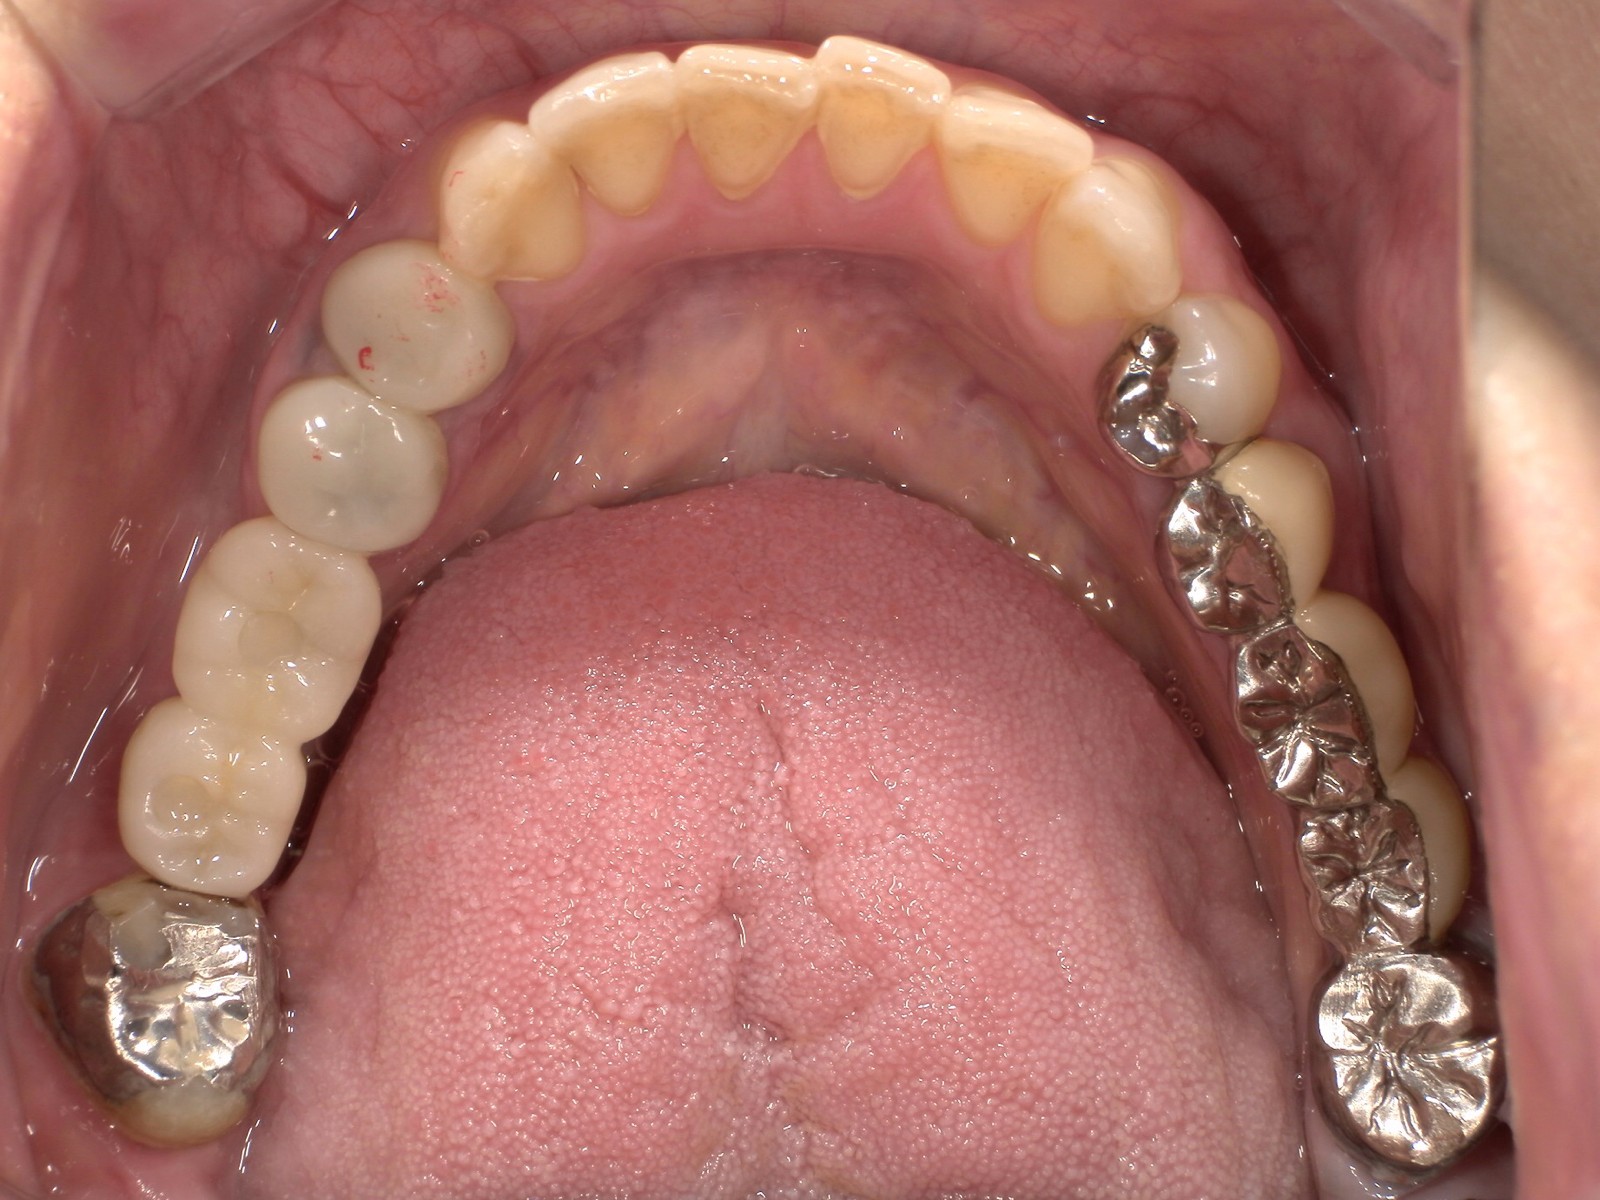

CASE 02

Before

After

施術内容下の銀歯を白くしたいとのこと。下顎左右第一大臼歯の銀歯をジルコニアクラウンに交換。

治療期間2か月

リスク・副作用ジルコニアは非常に強度が高いですが、強い衝撃や極端に強い噛み合わせ、歯ぎしり・食いしばりなどがある場合、まれに割れたり欠けたりする可能性があります。

費用198,000円

※表示金額は全て税込みです。